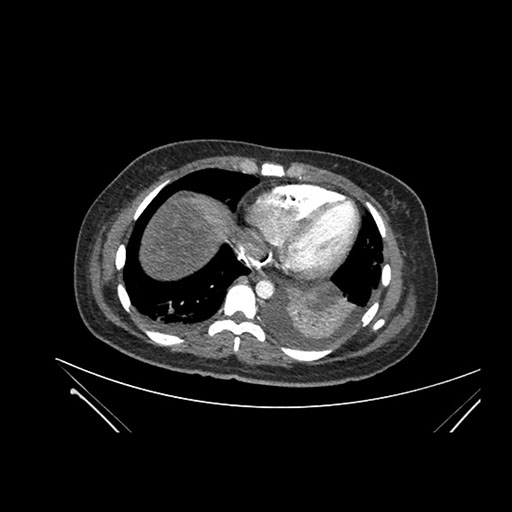

Imaging Analysis

Look through the patient's CT scan to identify any areas of concern for the necessary procedure.

Axial Venous